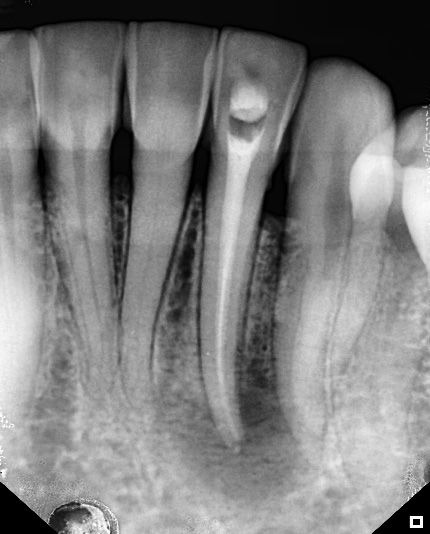

After 30 days, the patient returned and a new periapical radiograph was taken before the intracanal dressing was removed. This radiograph revealed that the periapical lesion had recovered (Figure 3). The intracanal dressing was removed with NaOCl irrigation, followed by a final rinse with EDTA and NaOCl, which was boosted with Easyclean.

Figure 3: radiographic situation after 30 days. Note the visible regression of the lesion